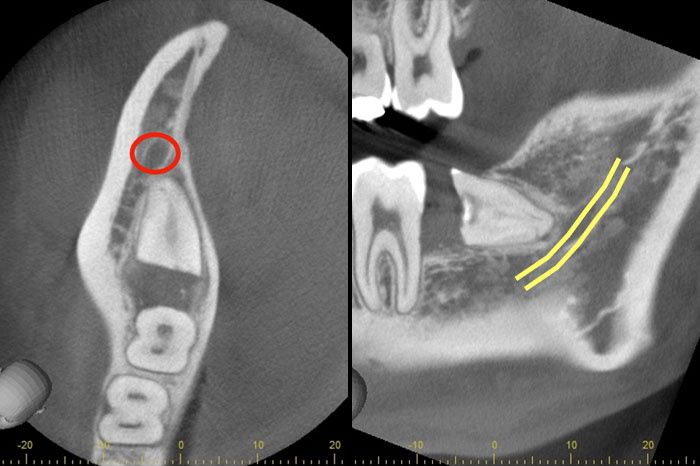

CTの画像です。下歯槽神経と親知らずはほんの少し接触していることがわかります。そのため、この親知らずは2回に分けて抜いていくことにしました。1回目は歯の頭の部分だけを切るだけになります。2回目は1−3ヶ月経ってから行います。

1回目で頭の部分を取ったスペースに歯が伸びてきますので、下歯槽神経と離れたかどうかを再びCTで確認して、残りの根の部分を抜いていく方法になります。

麻布十番歯科でのCT画像。親知らずの生え方を確認し2回に分けて抜歯を行う方法を選択

1回目から3ヶ月経ってからCTを撮影したものです。下歯槽神経の位置が根の先端から離れているのが確認できます。これで下歯槽神経を損傷させることなく、親知らずの抜歯を行うことができます。